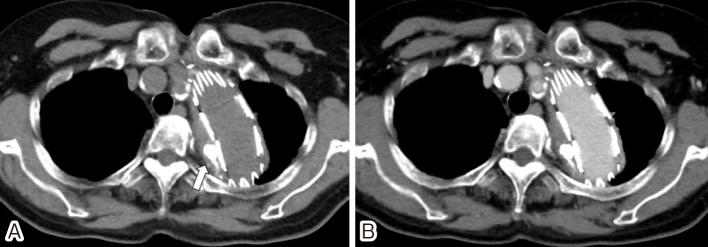

An 81-year-old woman presented with massive hemoptysis. She had a history of total arch replacement with an elephant trunk followed by concomitant antegrade thoracic endovascular aortic repair for the aortic arch and the descending aortic aneurysm. Computed tomography (CT) showed expansion of the aortic aneurysm with type II endoleak, lung parenchymal consolidation, and ground-glass opacity. An aortopulmonary fistula was suspected. Surgery posed a very high risk for the patient; hence, a less invasive approach was considered. Left subclavian arteriography revealed a type II endoleak. A transarterial approach would be difficult due to the small and tortuous access route and longer procedure time. Therefore, CT-guided puncture embolization was performed. She had no recurrence of hemoptysis for 1.4 years after the embolization.

一名81岁女性出现大量咯血。她有全弓置换并植入象鼻支架的病史,随后因主动脉弓和降主动脉瘤接受了同期顺行性胸段血管腔内主动脉修复术。计算机断层扫描(CT)显示主动脉瘤扩张伴II型内漏、肺实质实变和磨玻璃影。怀疑存在主动脉肺瘘。手术对该患者风险极高;因此,考虑采用侵入性较小的方法。左锁骨下动脉造影显示II型内漏。由于入路小且迂曲,手术时间长,经动脉途径困难。因此,进行了CT引导下穿刺栓塞术。栓塞术后1.4年,她未再出现咯血复发。